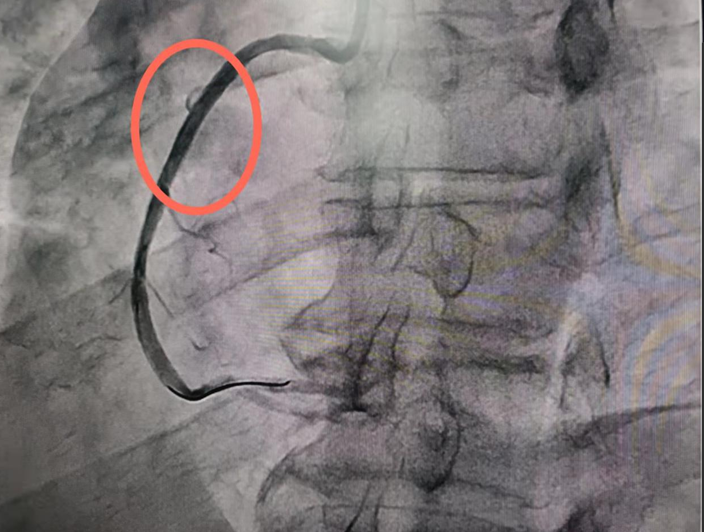

冠心病的介入治疗

冠心病的介入治疗,主要包括冠状动脉造影术、经皮冠状动脉球囊血管成形术(PTCA)、冠状动脉支架植入术(PCI)等。冠状动脉造影术即是在数字减影机下使用导管在冠状动脉内推注照影剂,检查冠状动脉有没有粥样硬化引起的狭窄,血流动力学的改变。冠状动脉球囊血管成形术是通过外周动脉,将指引导管送至待扩张的冠状动脉口,再将相应大小的球囊沿导引钢丝送到冠脉狭窄的节段,根据病变的特点用适当的压力和时间进行逐渐扩张,利用钝性扩张达到解除狭窄的目的。但是单纯PTCA可能会造成冠状动脉急性闭塞以及再狭窄的发生率较高。冠状动脉支架植入术与PTCA相同的是同样需要将相应大小的球囊沿导丝送入冠状动脉狭窄的节段,但不同在于球囊外有可扩张支撑的网状带间隙支架,随着球囊扩张,支架在冠状动脉内狭窄处扩张,球囊撤走后,支架留在冠脉内支撑血管壁,维持血流通常。

心病科自2011年开始开展冠心病科的介入治疗,相继开展了血管内超声检查(IVUS)腔内影像学检查及冠脉血流储备分数(FFR)功能学检查。尤其在急性心肌梗死的介入治疗、多支复杂病变、左主干病变、分叉病变及陈旧闭塞病变(CTO)的介入治疗达到国内先进水平。每年完成手术800余台次。

手术前